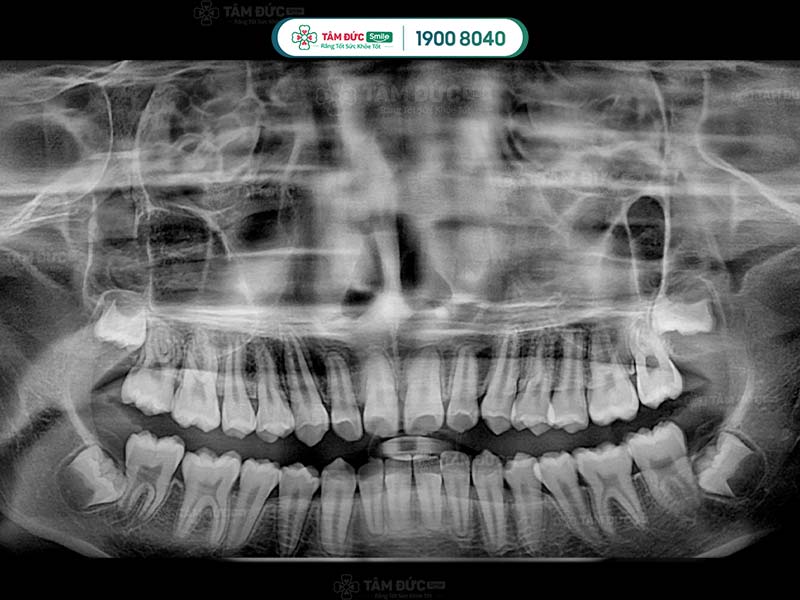

phim x-quang răng khôn

10.1. Chụp phim và tư vấn

Đây là bước quan trọng nhất trong quy trình nhổ răng khôn an toàn. Quý khách cần chụp phim X-quang để bác sĩ xác định vị trí và tư thế của răng khôn. Qua đó, bác sĩ dễ dàng đưa ra phương án nhổ răng an toàn nhất.